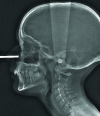

Made for a large technical public, this article wants to deliver key-elements required for the comprehension of dental and maxillo-facial radiology, from the intraoral 2D one to the recent 3D imaging.

Intraoral and extraoral techniques are both described with their National and International standards after a brief recall of the radiation protection procedures applicable in the dental field.

The intra- and extra-oral dental radiological examinations described here are considered to be first-line when they are minimally invasive and easy to perform in the office. If necessary, volumetric imaging can be used as a second line of defence, as it is less energy-efficient in terms of radiation but provides a wealth of three-dimensional information, and is becoming increasingly important for complex treatment plans. The recent arrival, spectacularly rapid spread and technical evolution of CBCT have had a major impact on dental practice, to the extent that new indications (HAS), new codes (CCAM) and appropriate training have become essential. What's more, indications that used to involve CT scans are now being redirected towards CBCT, thereby limiting patient dose.